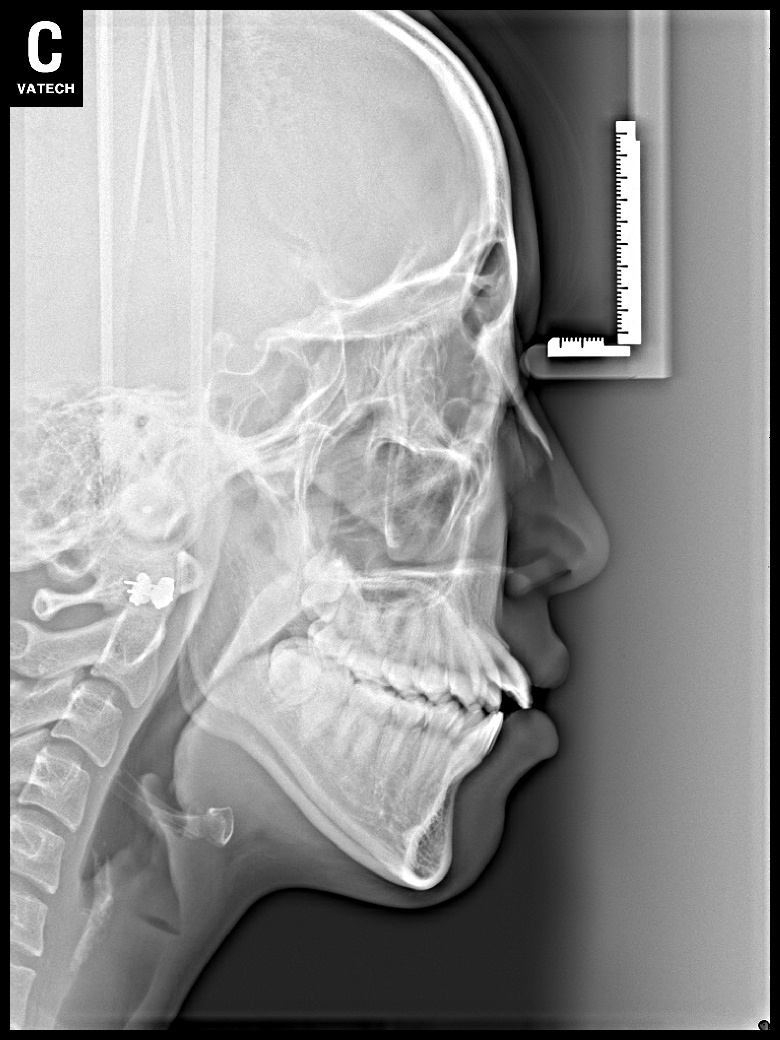

치료 전 사진입니다.